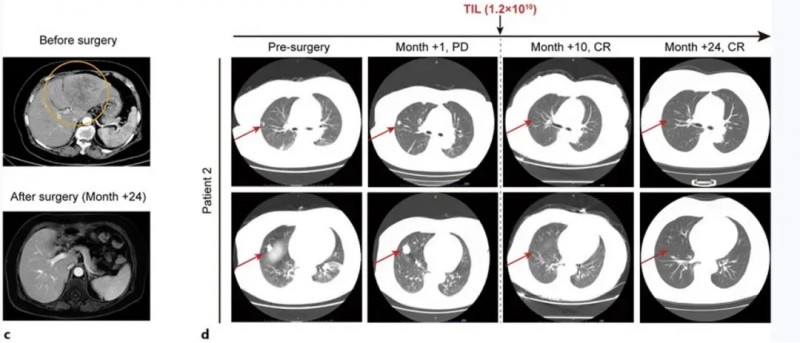

患者2为一例67岁女性,因肝癌破裂出血接受经肝动脉栓塞术后1周入院。CT示肝左叶147×79mm混合信号肿块,双肺多发散在结节(右肺中叶最大18mm),甲胎蛋白(AFP)14,529ng/mL,确诊为HBV相关性肝细胞癌(BCLCC期)。该患者入组后接受姑息性左半肝切除术,肿瘤组织经29天培养获得TIL细胞;后续依次接受淋巴细胞清除治疗、自体TIL细胞单次输注、IL-2治疗及特瑞普利单抗治疗(共18个疗程)。

结果显示:肝切除术后1个月肺转移灶出现进展(右肺结节增大至25mm);但经TIL联合抗PD-1治疗后,术后10个月肺病灶完全消退,截至随访24个月,患者持续无瘤生存(详见下图c、d)。

▲图源“Liver Cancer”,版权归原作者所有,如无意中侵犯了知识产权,请联系我们删除